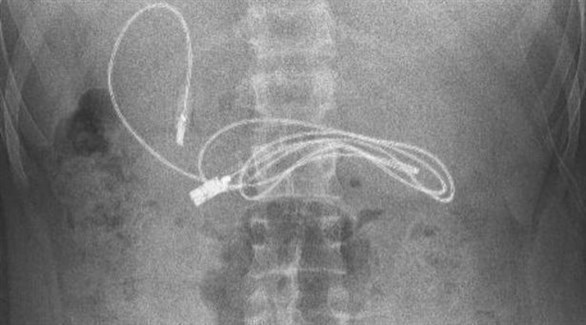

صدم مراهق الأطباء، بعد نقله إلى أحد مستشفيات تركيا وهو يعاني من غثيان شديد وآلام مبرحة في معدته، إذ أظهرت الأشعة المقطعية، ابتلاعه سلك شاحن طوله 90 سنتيمتراً.

وخضع المراهق الذي لم تكشف هويته، إلى عملية عاجلة لاستخراج السلك من معدته، ليتبين أنه ابتلع ربطة شعر، أيضاً، حسب صحيفة ميرور البريطانية.

وقال الطبيب الذي أشرف على الجراحة، إن العملية كانت معقدة لأن أحد طرفي السلك مَر إلى الأمعاء الدقيقة. ولحسن الحظ، تعافى المراهق، 15 عاماً، سريعاً بعد العملية وعاد إلى منزله في ديار بكر بصحة جيدة.